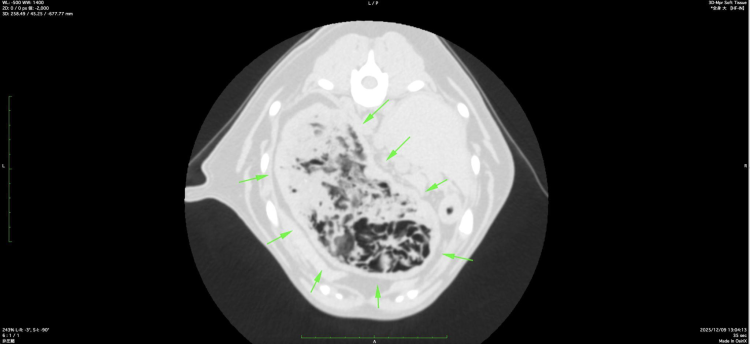

より詳しい評価のため、CT検査を実施しました。

CTでは、胃内に明らかな人工物は確認できなかったものの、胃の中に何らかの内容物が大量に存在していることが分かりました。

胃のCT検査画像